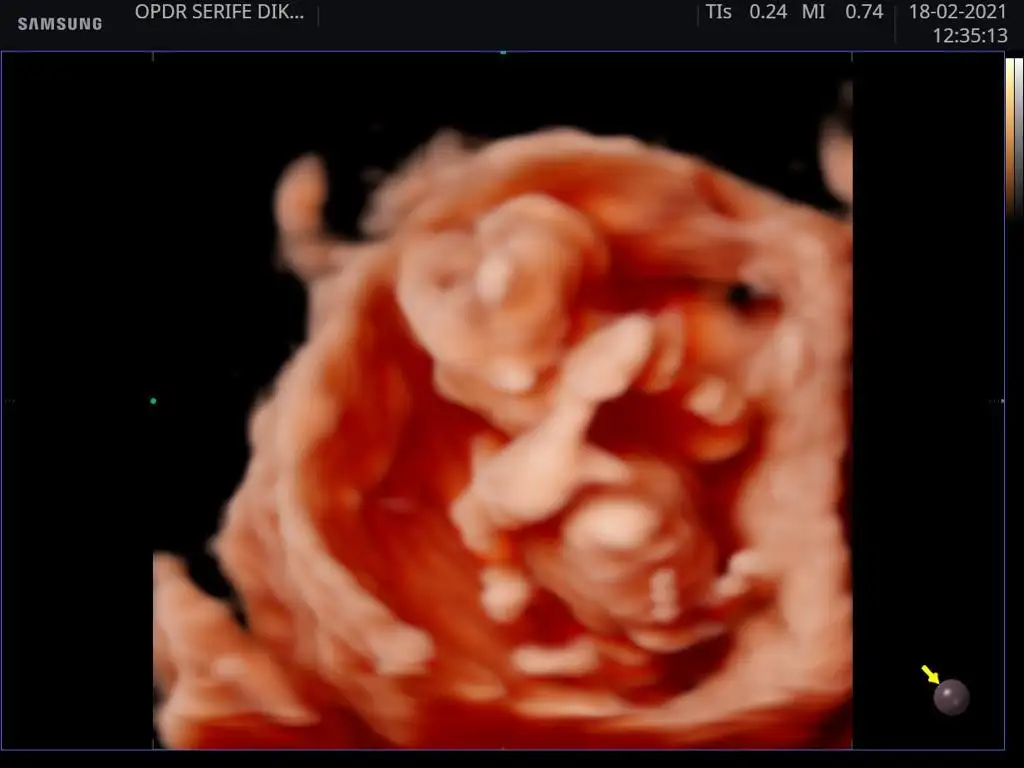

Anlamıyorum ki dediğim gibi doktorum /80 erkek dedi bu renkli de baktı ama değişir dedi ikili taramada bakmıstı. Valla sağlıklı olsunda ne yalan söyleyim bir tane de oğlum olsun isitlrjm 😀

Tamam canım teşekkür ederim doktor /80 erkek dedi ama değişebilir dedi 😀 bir kızım var hayırlısı ne ise o olsun